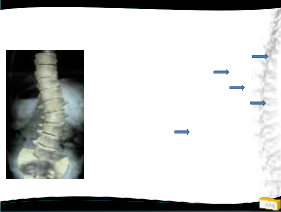

Radyolojik bulgular

• Apeks L2 ya da L3’de

• Rotasyon, laterale kayma

(derecelendirilir)

• Genellikle oldukça fleksibl, üstte kompansatuvar eğrilik kısa ve pek az

• Lomber hipolordoz

• Osteofitler (cerrahi

planlamada önemli)